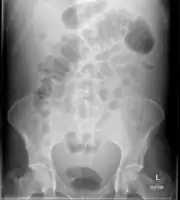

Diagnosis

Routine complete blood count (CBC), basic metabolic profile, liver enzymes, and coagulation should be performed. Most experts recommend a diagnostic paracentesis be performed if the ascites is new or if the person with ascites is being admitted to the hospital. The fluid is then reviewed for its gross appearance, protein level, albumin, and cell counts (red and white). Additional tests will be performed if indicated such as microbiological culture, Gram stain and cytopathology.[6]

The serum-ascites albumin gradient (SAAG) is probably a better discriminant than older measures (transudate versus exudate) for the causes of ascites.[10] A high gradient (> 1.1 g/dL) indicates the ascites is due to portal hypertension. A low gradient (< 1.1 g/dL) indicates ascites of non-portal hypertensive as a cause.

Ultrasound investigation is often performed prior to attempts to remove fluid from the abdomen. This may reveal the size and shape of the abdominal organs, and Doppler studies may show the direction of flow in the portal vein, as well as detecting Budd-Chiari syndrome (thrombosis of the hepatic vein) and portal vein thrombosis. Additionally, the sonographer can make an estimation of the amount of ascitic fluid, and difficult-to-drain ascites may be drained under ultrasound guidance. An abdominal CT scan is a more accurate alternate to reveal abdominal organ structure and morphology.